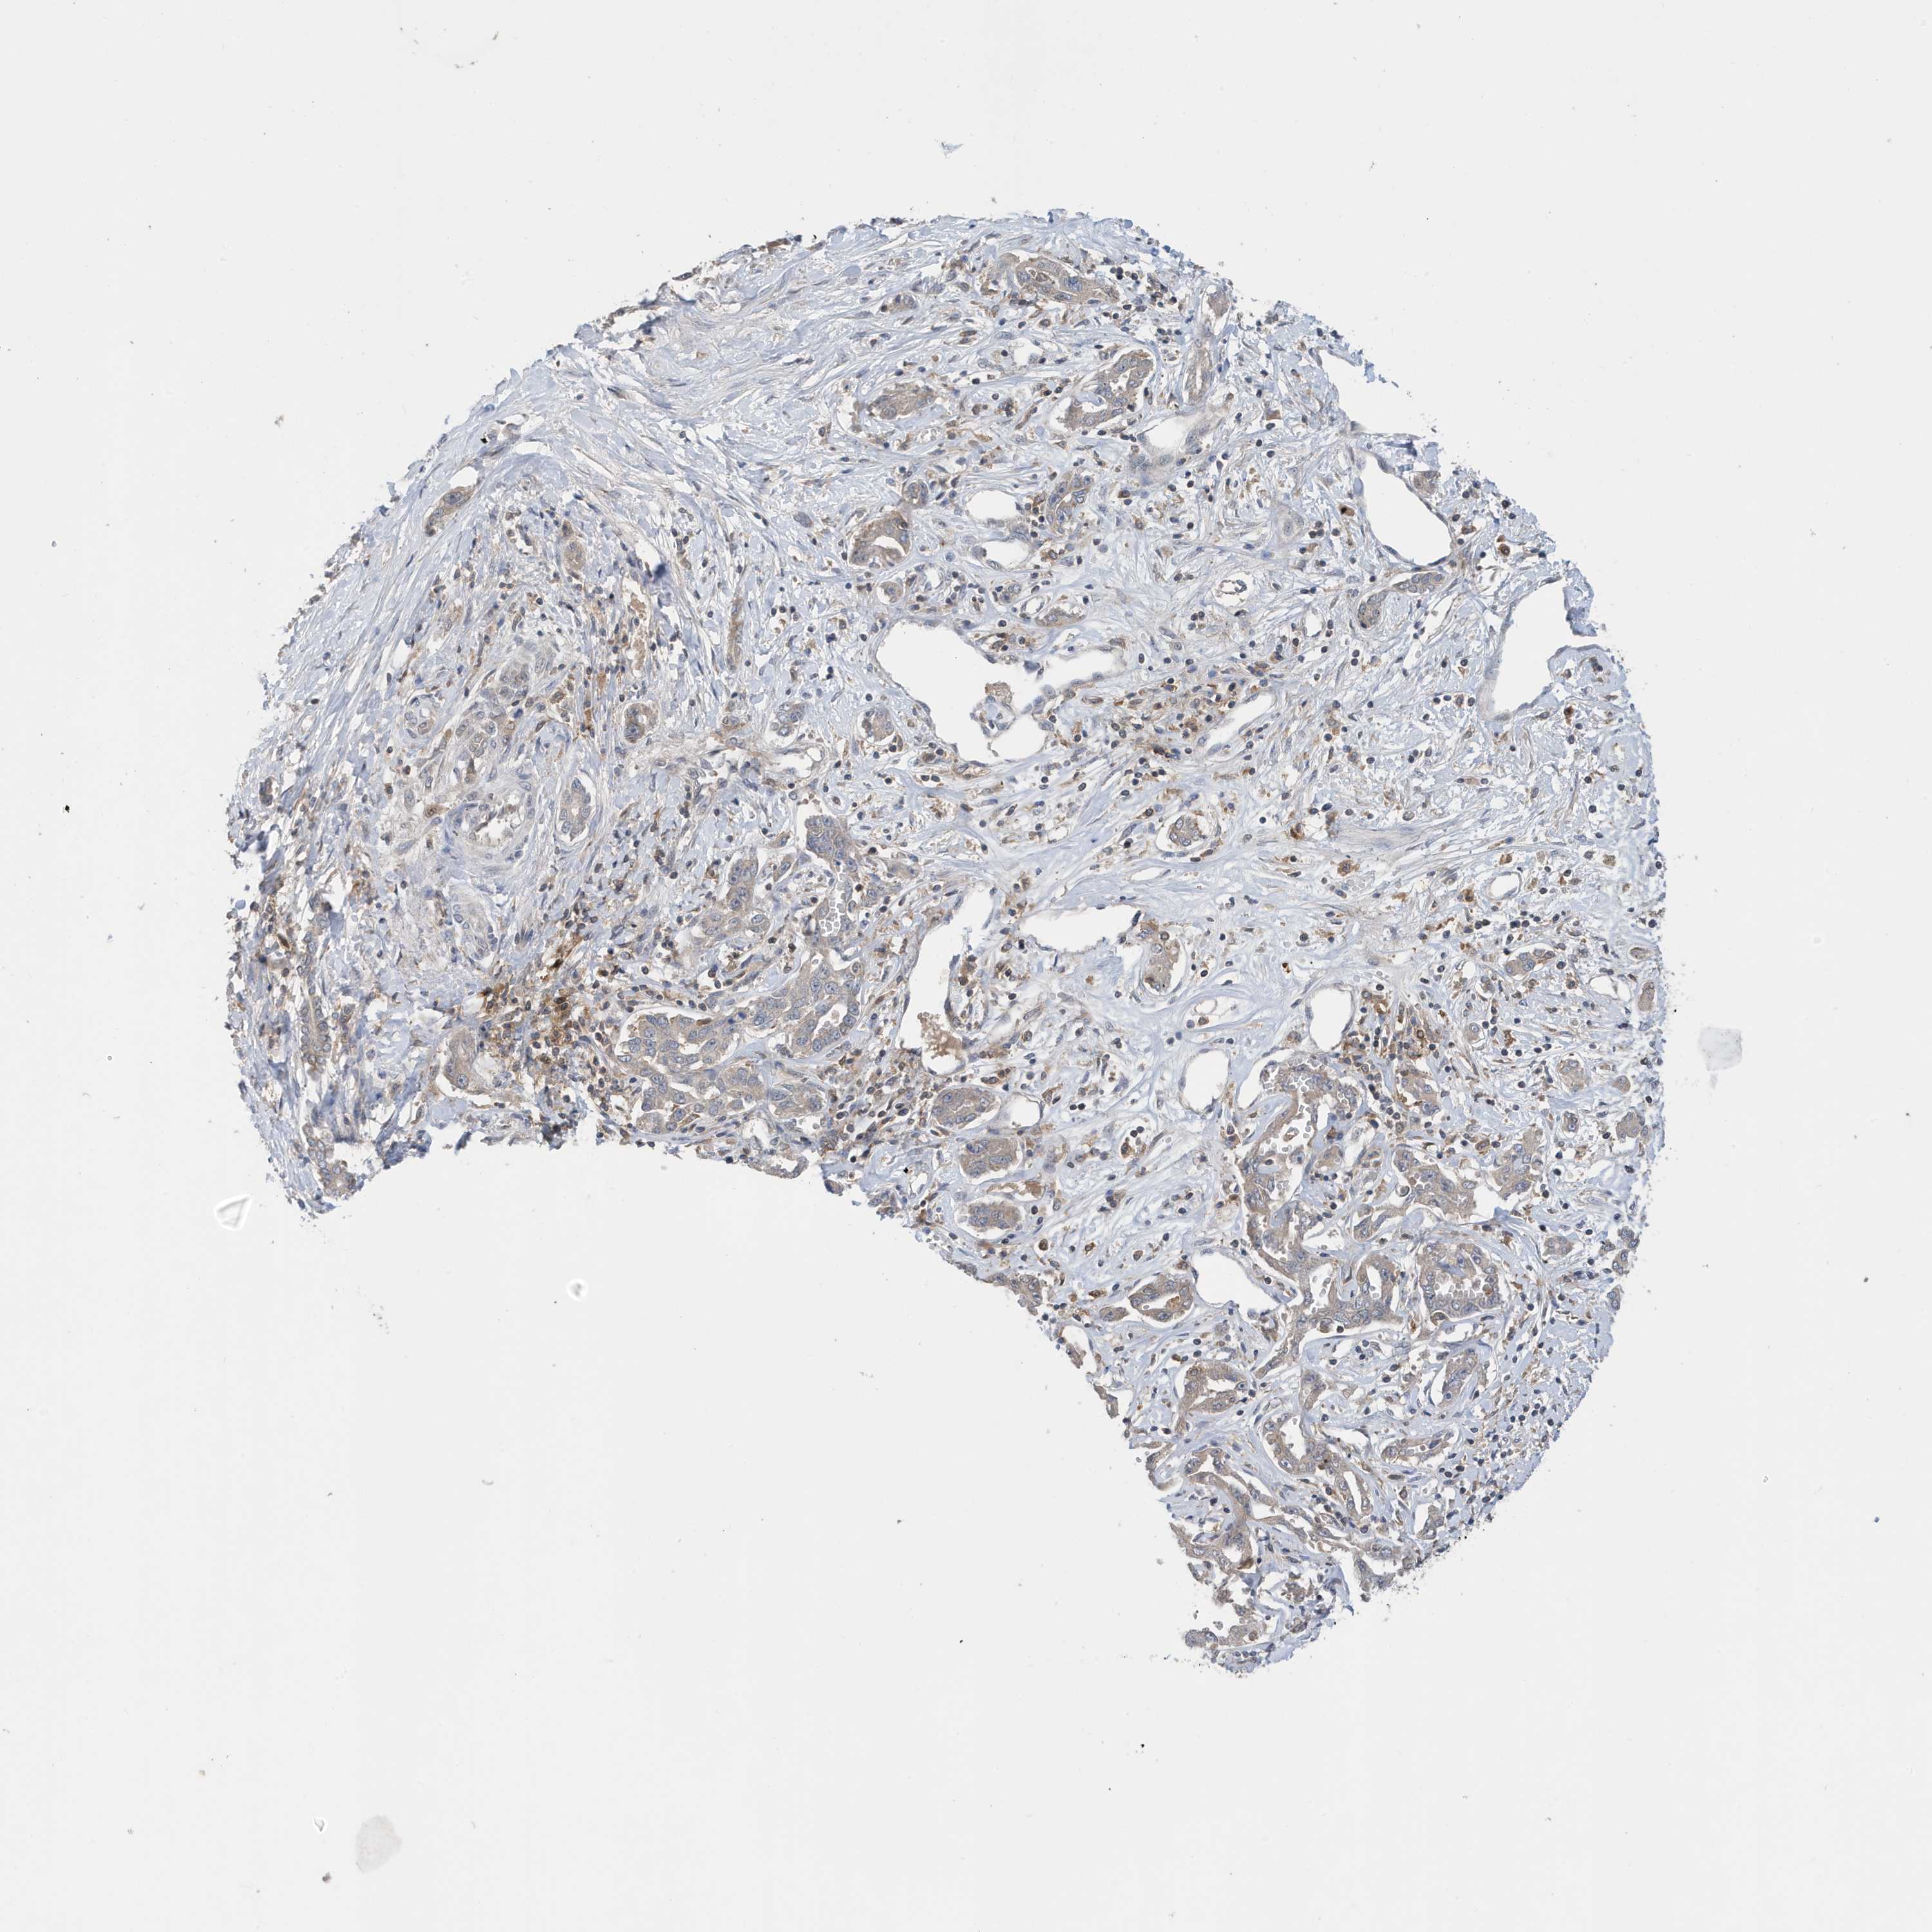

LIVER CANCER - Protein expressioni

A mouse-over function shows sample information and annotation data. Click on an image to view it in a full screen mode. Samples can be filtered based on level of antibody staining by selecting one or several of the following categories: high, medium, low and not detected. The assay and annotation is described here.

Note that samples used for immunohistochemistry by the Human Protein Atlas do not correspond to samples in the TCGA dataset.

Antibody stainingi

Antibody staining in the annotated cell types in the current human tissue is reported as not detected, low, medium, or high, based on conventional immunohistochemistry profiling in selected tissues. This score is based on the combination of the staining intensity and fraction of stained cells.

Each image is clickable and will lead to virtual microscopy that enables deeper exploration of all samples and also displays staining intensity scores, fraction scores and subcellular localization as well as patient and tissue information for each sample.

Antibody HPA036181

Staining

High

Medium

Low

Not detected

Intensity

Strong

Moderate

Weak

Negative

Quantity

>75%

75%-25%

<25%

None

Location

Nuclear

Cytoplasmic/membranous

Cytoplasmic/membranous,nuclear

Cholangiocarcinoma

Carcinoma, Hepatocellular, NOS